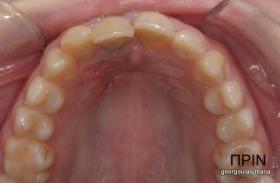

Η κοπέλα αυτή ήρθε στο ιατρείο με κάταγμα στον δεξιό άνω κεντρικό τομέα. Το δόντι είχε απονευρωθεί στο παρελθόν και είχε αποκατασταθεί με βιδωτό άξονα κ ανασύσταση με ρητίνη και το αισθητικό αποτέλεσμα ήταν φτωχό. Η ασθενής ήθελε να είναι καλυμμένη αισθητικά για όσο χρονικό διάστημα θα διαρκούσε η θεραπεία. Πραγματοποιήθηκε τομογραφία κωνικής δέσμης (CBCT) στην περιοχή και αποφασίστηκε να γίνει εξαγωγή του δοντιού, διατήρηση του όγκου του φατνίου και 3 μήνες μετά τοποθέτηση εμφυτεύματος με ταυτόχρονη χρήση μοσχευμάτων σκληρών κ μαλακών ιστών  για βέλτιστο αισθητικό αποτέλεσμα. Το εμφύτευμα αποκαταστάθηκε με υβριδικό κολόβωμα από διπυριτικό λίθιο και ολοκεραμική στεφάνη από διπυριτικό λίθιο (Emax). Καθ’ όλη τη διάρκεια της θεραπείας, η ασθενής ήταν καλυμμένη αισθητικά με γέφυρα Meryland  συγκολλημένη στα δύο διπλανά δόντια. Μετά την οστεοενσώματωση του εμφυτεύματος και πριν την τελική αποκατάσταση, τοποθετήθηκε στο εμφύτευμα προσωρινή εργασία με σκοπό τη βελτίωση των ούλων.